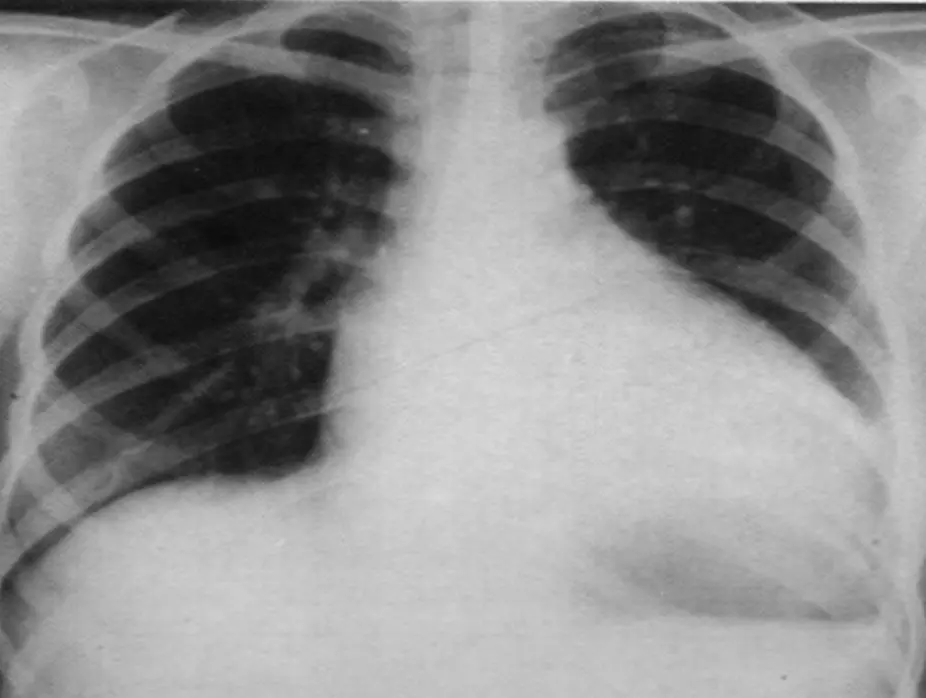

Chest Radiography

- Cardiomegaly: Left-to-right shunting defects, Dilated cardiomyopathy, Myocarditis, and Pericardial effusion.

- Pulmonary congestion/pulmonary edema.

- Pleural effusion.

- Pericardial effusion.

Chest radiograph of a 13-year-old boy with dilated cardiomyopathy